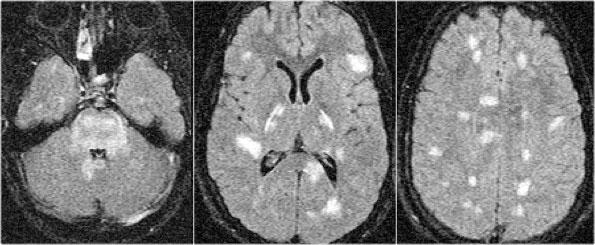

Viêm mạch máu

Các hình ảnh thuộc về một trẻ em có biểu hiện đau đầu, sốt, tăng cảm giác đau và tê bì nửa người trái.

Bệnh nhân cũng có liệt dây thần kinh vận nhãn ngoài (dây VI).

Các hình ảnh không đặc hiệu với nhiều tổn thương khu trú và chẩn đoán đầu tiên có thể nghĩ đến là xơ cứng rải rác (MS).

Chẩn đoán phân biệt bao gồm viêm, nhiễm trùng và di căn.

Trong những trường hợp như vậy, cần thực hiện hình ảnh cắt ngang cột sống để xác định vị trí chính xác của tổn thương và chụp MRI não.

Tiếp tục.

Các tổn thương nằm ở phía lưng và một trong số đó có ngấm thuốc tương phản từ.

Nếu đây là nhiễm trùng hoặc di căn, việc không phải tất cả các tổn thương đều ngấm thuốc sẽ là điều bất thường.

Xơ cứng rải rác (MS) vẫn còn trong danh sách chẩn đoán của chúng ta.

Tiếp tục với MRI não.

Trên chuỗi xung T1W có tiêm thuốc tương phản từ (CE-T1WI), chỉ có một tổn thương ngấm thuốc.

Vị trí của các tổn thương và đặc điểm ngấm thuốc có thể phù hợp với chẩn đoán xơ cứng rải rác (MS), nhưng trường hợp này được xác định là viêm mạch máu.

Viêm mạch máu có thể là vô căn, nhưng cũng gặp trong lupus ban đỏ hệ thống (SLE), hội chứng Sjögren và bệnh Behçet.

Thông thường, viêm mạch máu được nghĩ đến như một bệnh lý của các mạch máu trong não, nhưng tất cả các dạng viêm mạch máu đều có thể biểu hiện ở cột sống.

Bệnh tạo ra hình ảnh tương tự xơ cứng rải rác (MS).